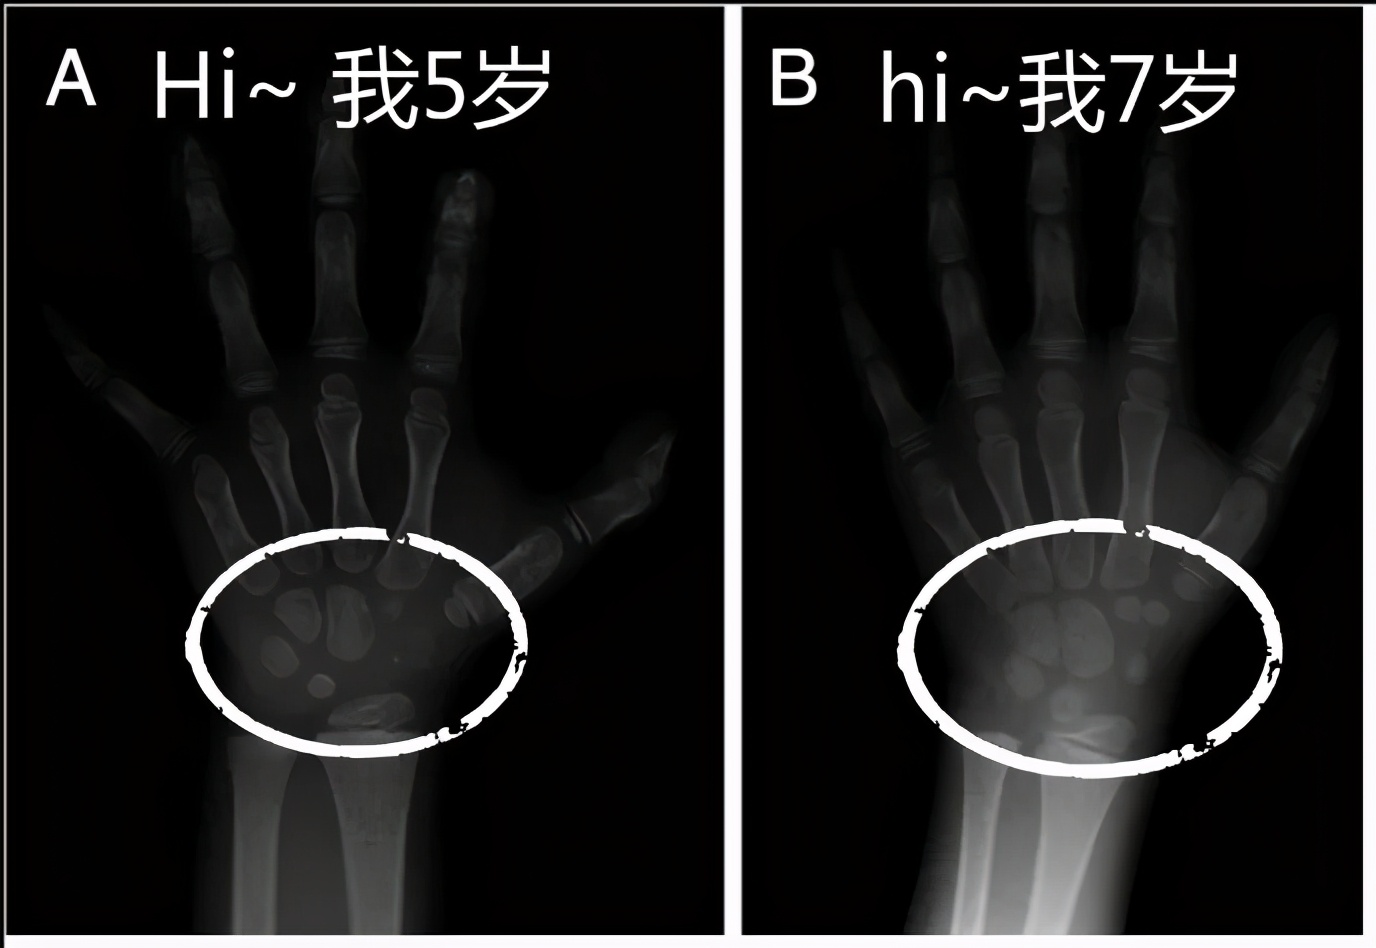

测骨龄过程很简单,就是给宝宝左手正位拍个X光片,几分钟就完事。

医生主要根据《中国人手腕骨发育标准-CHN法》人工读片分析(有的地方已经计算机读片),算出骨龄。

你可以笼统地理解成,医生把宝宝X光片和不同年龄的、标准左手X光片对比,接近哪个,就是几岁。

手的骨骼发育示意图(图源:Schmitt and Lanz 2008)

这样算出来的骨龄,再和真实年龄比较:

骨龄和年龄差在±1岁内——发育正常。

骨龄>年龄1岁,不超过2岁——发育提前。

骨龄<年龄1岁,不超过2岁——发育落后。

骨龄<年龄2岁以上——发育异常落后。

骨龄>年龄2岁以上——发育异常提前。